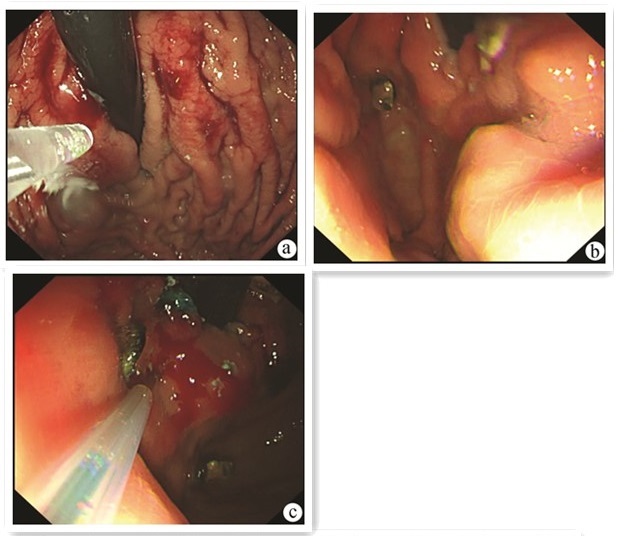

Splenic infarction and repeated abdominal infection after endoscopic therapy for esophagogastric varices

Jiali MA, Lingling HE, Yu JIANG, Hongshan WEI, Ping LI

2022, 38(9): 2113-2115. DOI: 10.3969/j.issn.1001-5256.2022.09.030

Abstract(972) HTML (239) PDF (2430KB)(72)

Abstract: